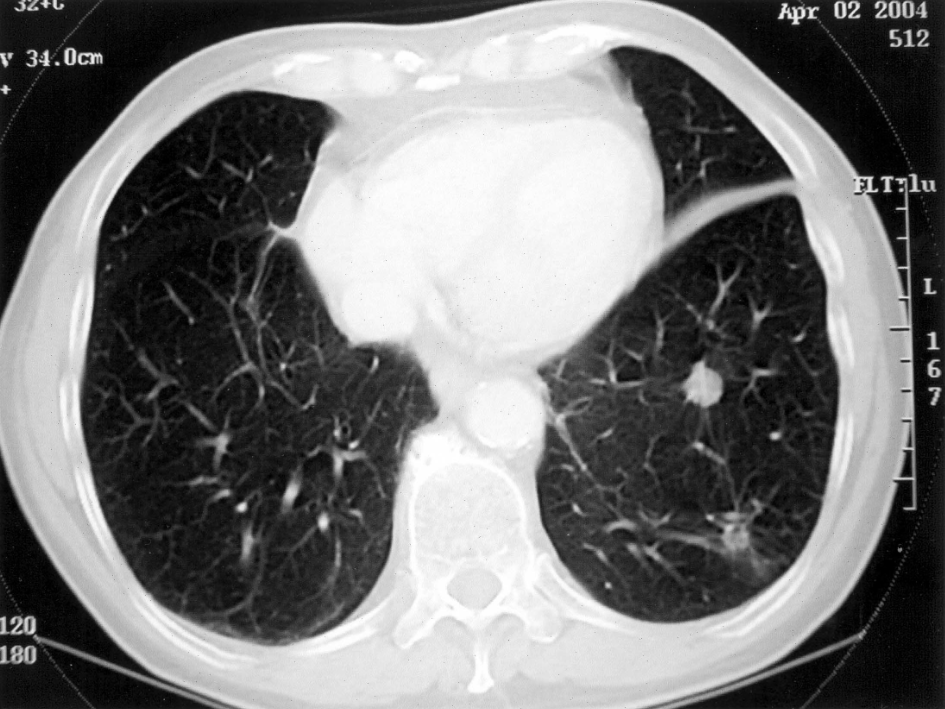

A 78-year old man with an advanced form of lung cancer (malignant fibrous histiocytoma) declined conventional cancer therapy and elected to adhere a daily regimen of 15 grams of omega-3 fish oils (8160 mg EPA, 6840 mg DHA) and over a 4-year period experienced a remarkably slow and steady decrease in the size and number of lung tumors. (see accompanying photos). [Nutrition & Cancer 2005]

Photo credits: Taylor & Francis, Nutrition & Cancer, Volume 52, 2005

(CT) scan performed on July 24, 2000 reveals two large masses in the lower left lobes of the lung.

CT scan performed on April 2, 2004. Tumor masses in lower left lobe are greatly diminished in size.